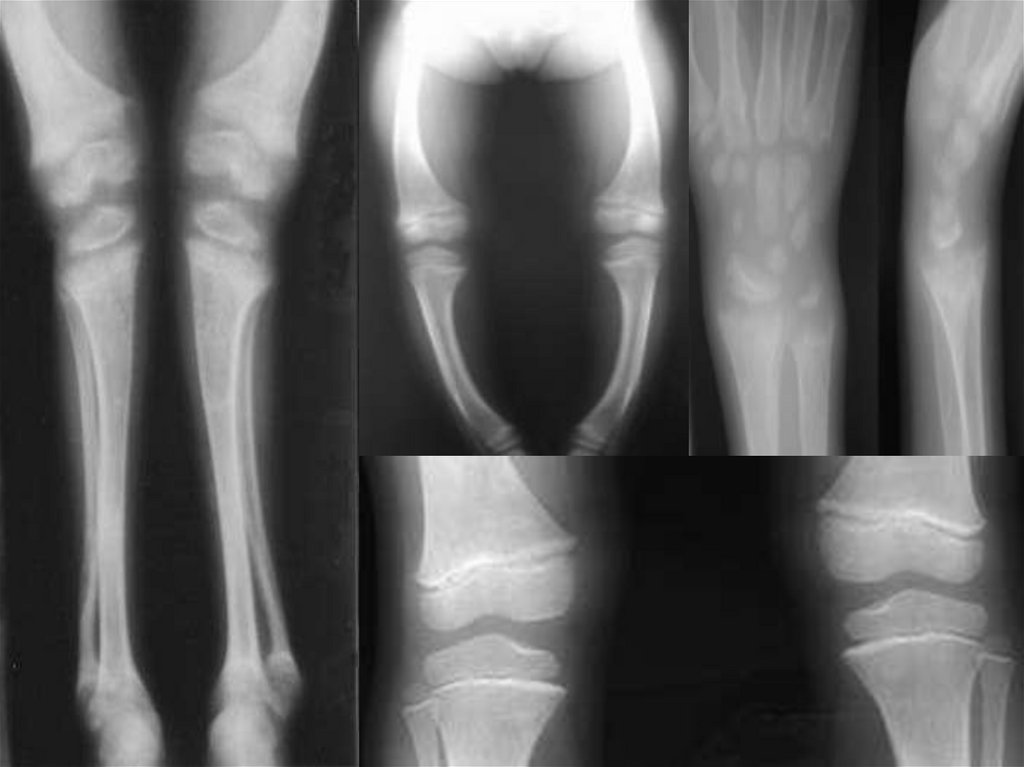

3. Рентгенограмма костей скелета –

остеопороз.

13. III степень

1. Деформация костей черепа, грудной клетки, позвоночника

+ разнообразные изменения трубчатых костей:

a) верхние конечности:

искривление плечевой кости и костей предплечья;

Деформация в области суставов: «браслеты» (утолщение в

области лучезапястных суставов), «нити жемчуга»

(утолщение в области диафизов фаланг пальцев).

б) нижние конечности:

искривление бедер вперед и кнаружи;

разнообразные искривления нижних конечностей (О- или

Х- образные деформации,);

деформации в области суставов.